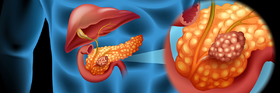

سرطان الپنكرياس

مقالة مفصلة: سرطان الپنكرياس

| سرطان الپنكرياس | ||

| معدل الانتشار | 393.800 (2015)[7] | |

| معدل البقاء 5 سنوات | 5%[11][17] | |

| حالات الوفاة | 411.600 (2015)[6] | |

| عوامل الخطورة | تقدم العمر، تدخين السجائر. ويمكن أن يكون من عوامل الخطورة أيضا التهاب الپنكرياس (المعثكلة) المزمن والداء السكري وتشمع (تليف) الكبد cirrhosis. معدل الحدوث أعلى في الدول ذات الغذاء الغني بالدهون، المرض أكثر شيوعا عند السود منه عند البيض. وقد ارتفع معدل الوفيات قليلا عند النساء السوداوات. | |

| العلامات المنذرة | عادة لا يوجد أي علامات منذرة حتى يستفحل المرض. | |

| الكشف والتشخيص | عن طريق الخزعة.

| |

| العلاج | من الصعب علاج الأورام التي ليست صغيرة ولا تقتصر على الپنكرياس.

| ملاحظات | * عندما يكون حجم الورم أقل من سنتيمترين ومحصورا فقط برأس الپنكرياس، وهو نهاية الپنكرياس المتصلة بالأمعاء، فإن الجراحة تجعل معدل البُقيا خمسَ سنوات نحو %20.